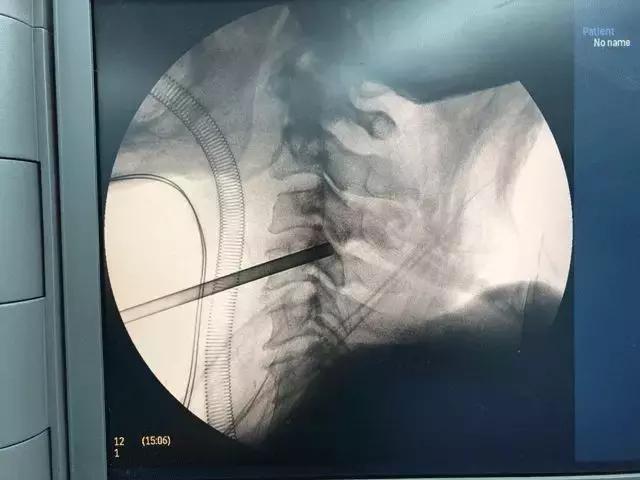

在椎体上“打洞”,直达突出椎间盘

术被安排春节前的最后一个工作日。手术当天,谢林教授在老人颈前使用经椎体穿刺的方法,在椎体上『打洞』,直达突出椎间盘,完成了一种新的颈椎微创手术方式。而在此之前,以往的颈前路手术则是通过椎间隙穿刺,摘除间隙后方的椎间盘突出,无法处理超过椎间隙水平的突出。